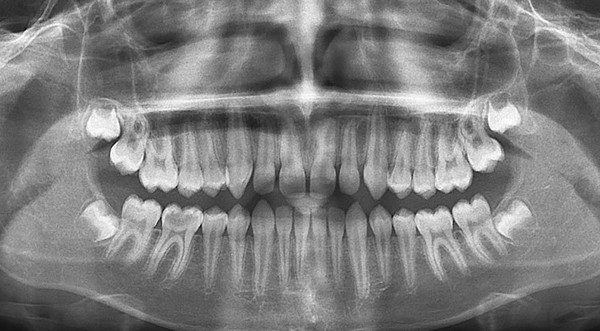

Панорамный снимок зубов (ОПТГ)

Порой для диагностики состояния полости рта Пациента недостаточно просто сделать снимок одного зуба, Врачу стоматологу важно видеть картину целиком. Кроме зубов, их корней, каналов, наличия пломб и коронок, на панорамном снимке видно состояние тканей пародонта, гайморовых пазух, синусов. Панорамный снимок зубов, или ортопантомограмма, позволяет обнаружить скрытые кариозные полости, воспаления, кисты, абсцессы, наличие пародонтальных карманов, выявить точное состояние корней и околозубных тканей, оценить состояние гайморовой пазухи, височно-нижнечелюстного сустава.

Также сделать ортопантомограмму необходимо при:

- планировании ортодонтического лечения брекетами или элайнерами;

- процессе подготовки к имплантации зубов;

- определении положения и состояния зубов мудрости.

Делается на ортопантомографе.